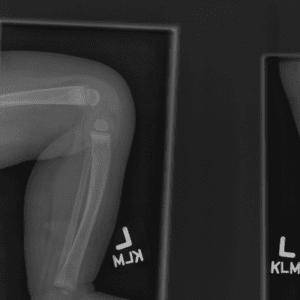

Pediatric Radiographs